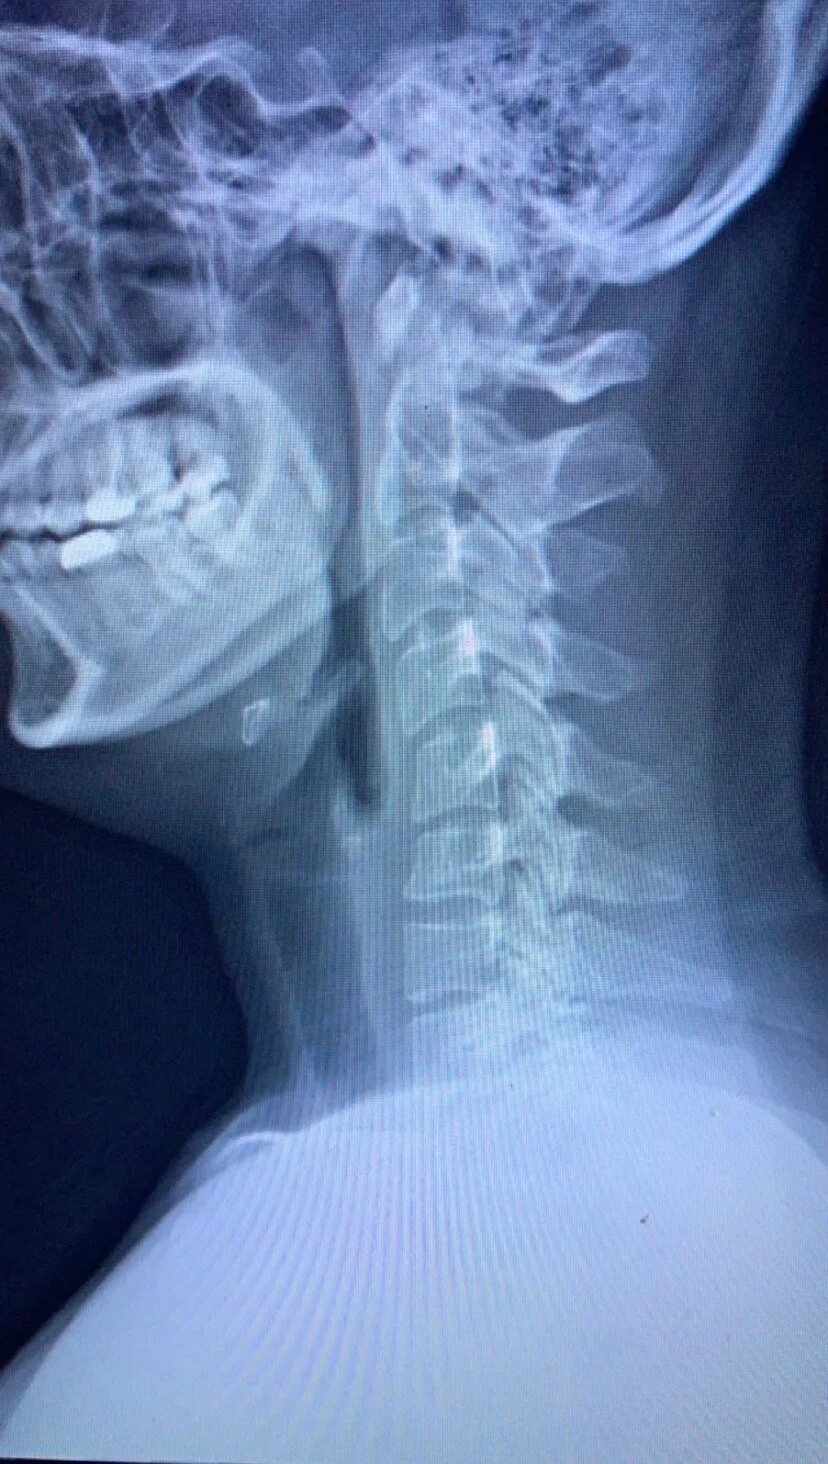

Zeleen had been a marathon runner before the accident, and ran 5+ miles most days. But shortly after getting home following her accident shooting pain began developing in her back, eventually forcing us to take her to urgent care. X ray scans indicated that Zeleen had two herniated discs and two bulging discs in her neck and back. The doctor told her, “you now have the back of a 70-year-old” and that she would not lift more than 20 pounds again for the rest of her life.

No jumping, no impact sports, no more marathons. The condition was irreversible.